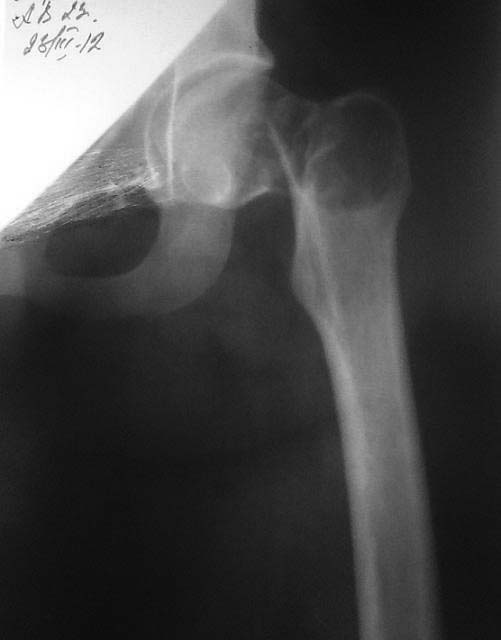

Патологический перелом шейки бедра

Пациентка 23 года срок беременности 22 недели. Травма низкоэнергетическая ( падение на бок ).

Отмечает наличие болевого синдрома в области т/б сустава около 1 года. Планируем остеосинтез (гамма стержнем или DHS) + биопсия.

По представленному снимку на первое место я бы поставил гигантоклеточную опухоль.

Судя по представленному снимку перелом в основание шейки бедра да еще с

костным дефектом. Фиксация должна быть стабильной чтобы поставить на ноги

перед родами и уходом за новорожденным. Фиксатор должен быть с угловой стабильностью - DHS, гвоздь желательно с двумя шурупами в шейку для ротационной стабильности. Если костный дефект большой можно использовать цемент и фиксатор ставить прежде чем цемент застынет. Биопсия конечно.

С учетом беременности правильно. Если это киста, она регенерирует после травмы и остеосинтеза, если это опухоль (например, ОБК) будете думать после биопсии, что делать и в какие сроки. На зло не похоже.